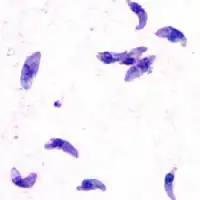

![]() Tachyzoity, rychle se množící asexuální stadium | |

Tachyzoit je oproti bradyzoitu mohutnější a má centrálně situované, dobře patrné jádro. Bradyzoit má jádro spíše v posteriorní části.

V hostiteli se vylíhne podlouhlý prvok dlouhý 4–8, tloušťky 2–3 mikrometry, se zužujícím se předním koncem a tupým zadním koncem. Uvnitř je dobře patrné jádro.